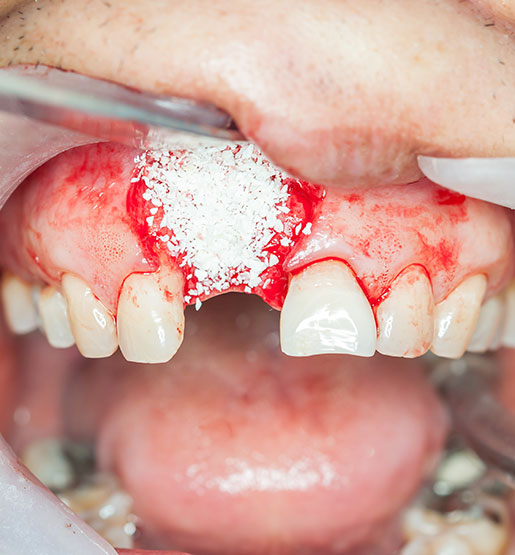

- Bio-oss: Este sistema está indicado para pacientes que van a colocarse un implante dental. Se trata de un compuesto por hidroxiapatita y calcio, dos elementos naturalmente presentes en los dientes. Por ello, es un material totalmente biocompatible con el organismo humano.

El injerto de hueso dental es un procedimiento que se realiza cuando el volumen óseo no es suficiente para sostener un implante. La necesidad y el momento de realizarlo se determinan con una valoración radiográfica detallada de cada caso.

Un injerto de hueso es un procedimiento preparatorio en implantología oral. Se realiza para asegurar que el implante dental tenga una base ósea sólida y suficiente para su correcta integración y estabilidad a largo plazo.